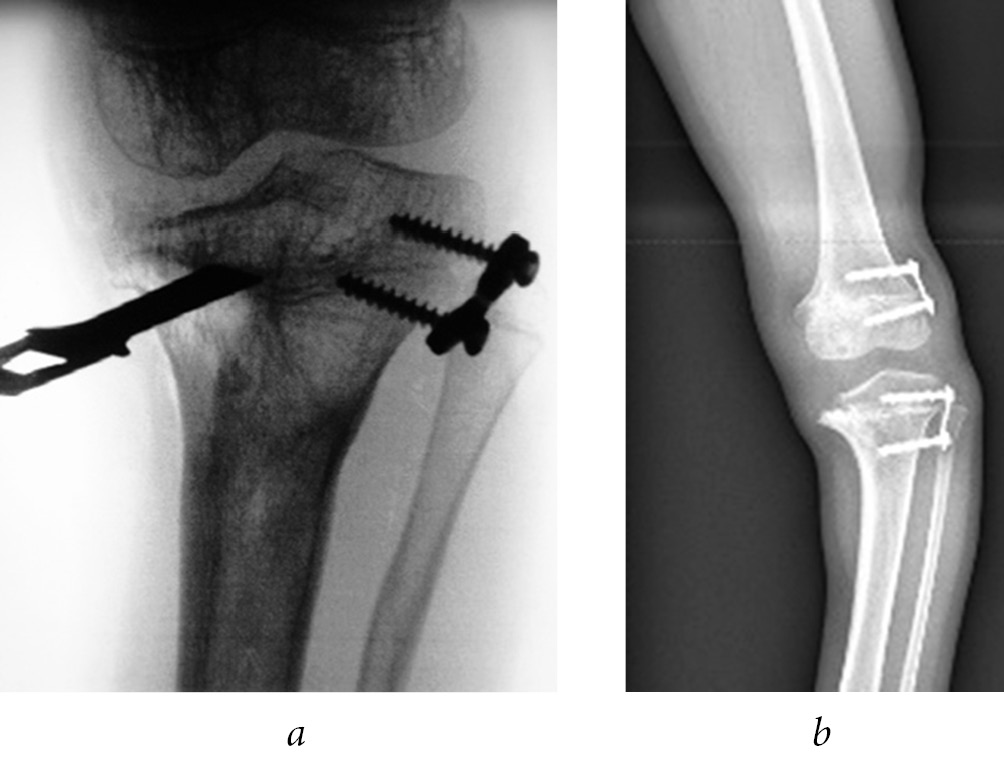

In four (33.3%) patients, the deformity correction was performed according to the controlled growth method by temporary epiphysiodesis of the actively functioning part of the bone growth zone with eight-shaped plates. Of which, the marginal synostosis of the growth zone was resected with subsequent hemiepiphysiodesis in two (16.7%) patients (Fig. 2).

Fig. 2. Resection of synostosis of the proximal growth zone of the left tibia (a) and variants of hemiepiphysiodesis of the functioning sections of the growth zones of the femur and tibia with eight-shaped plates (b)